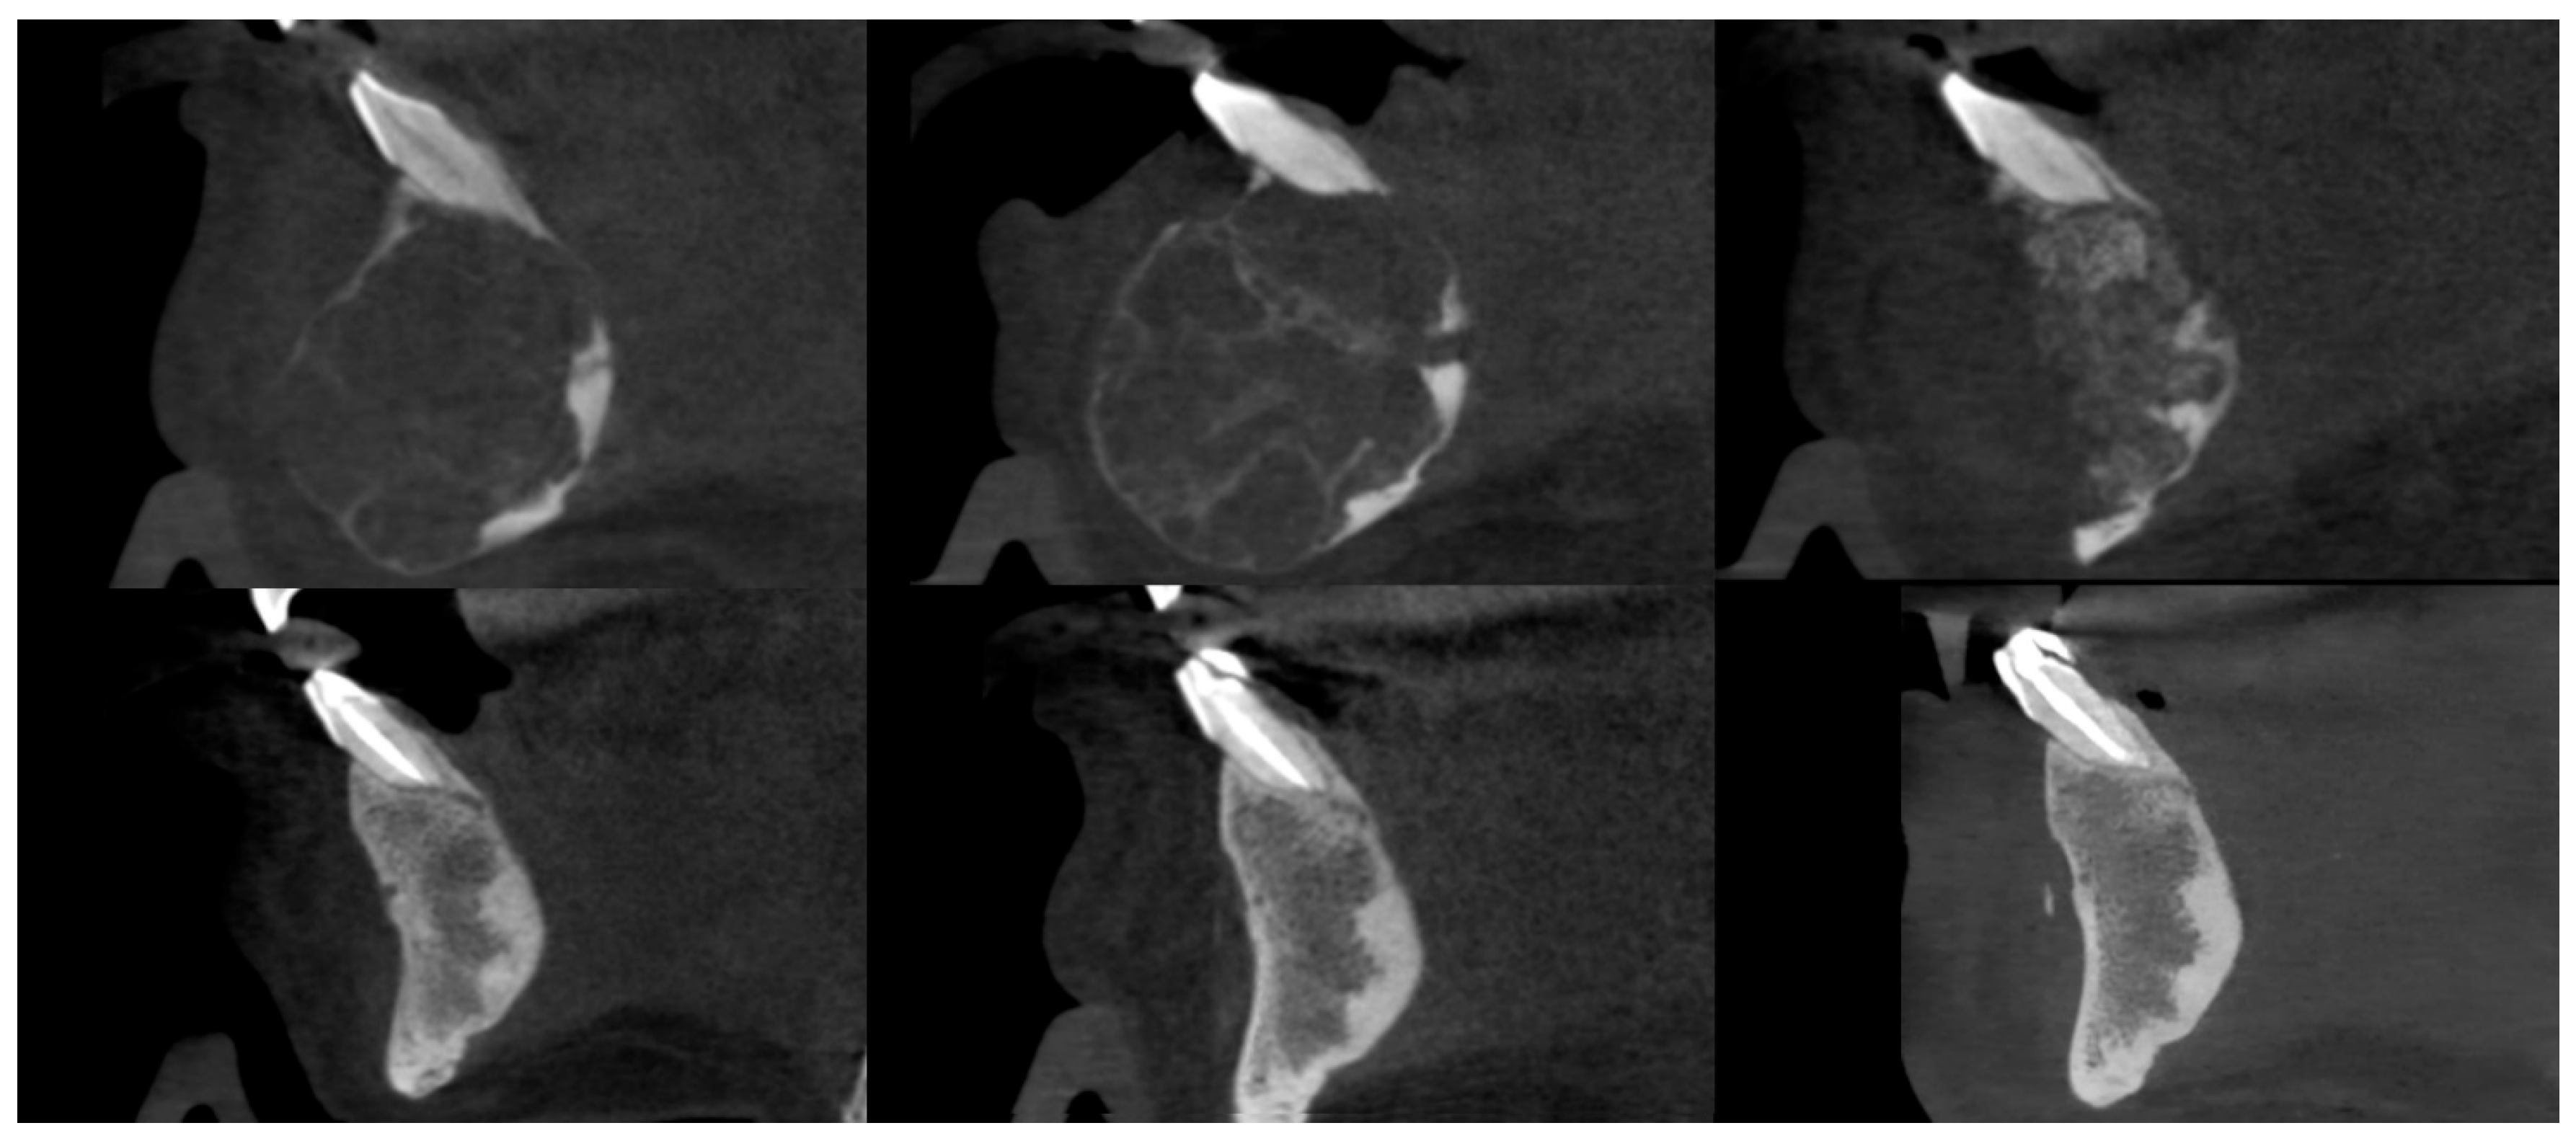

3.3. Osteosclerotic Rim (Peripheral Corticalization)